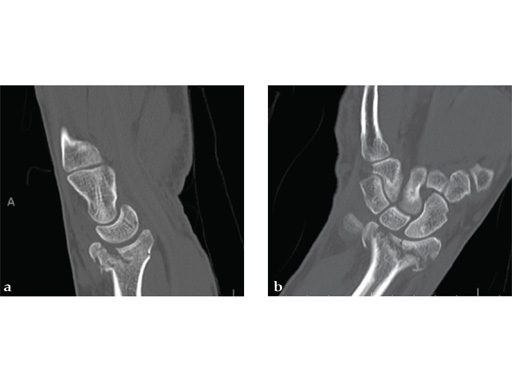

Case 1: A 62-year-old man fell on his outstretched left hand while playing tennis, sustaining an intraarticular fracture of the distal radius, Mller AO Classification 23-C3.2.

Case provided by Renato Fricker, Bruderholz, Switzerland